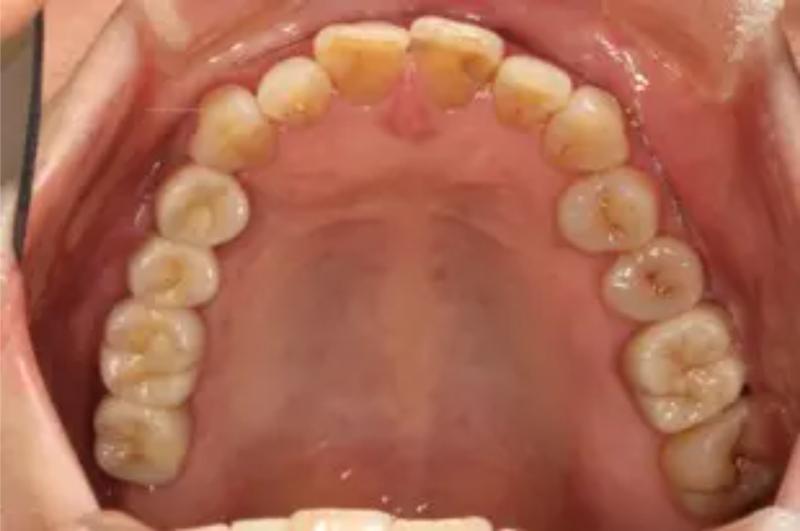

インプラント治療の症例紹介④

Before

After

主訴

義歯による疼痛

治療内容

下顎舌側に骨隆起があり義歯困難な状態。保存不可能な歯の抜歯を行い、インプラントを埋入し咬合再構成を行った。

治療費

2,851,200円(税込)

治療期間

29ヶ月

通院回数

26回

想定されたリスク

※咬合力の強い方なので、予防的にマウスピースの装着が必要。インプラント周囲炎の恐れがありました。

歯の欠損の対合歯の挺出等を修正し咬合平面を揃え咬合再構成を行った症例。